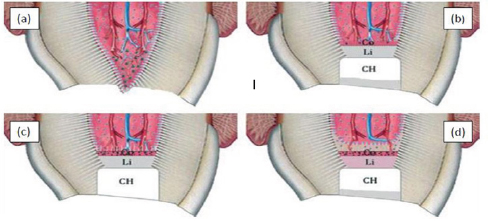

Figure 6: Calcium hydroxide and pulpal responses.

a) Exposed pulp, b) The high PH generates a zone liquefaction necrosis and a zone of coagulation necrosis, c) Sperical foci of calcification are formed that coalesce to form calcification zone and next to that collagen is formed, d) Bone like tissue is deposited containing cells and vascular inclusions.